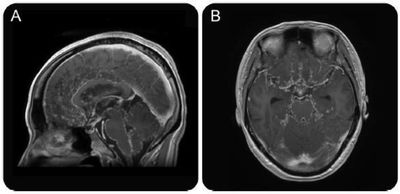

柔脑膜(包括软脑膜和蛛网膜,影像上难以鉴别)受累为中枢神经系统结节病最常见的表现,出现率高达 40%。表现为柔脑膜增厚及明显强化,强化可为弥漫性或结节样,好发于脑底部的脑膜,尤其是鞍上或额部,但可发生于脑膜的任何部位,更集中于脑沟深部。本例患者出现串珠样脑膜强化属于少见表现。